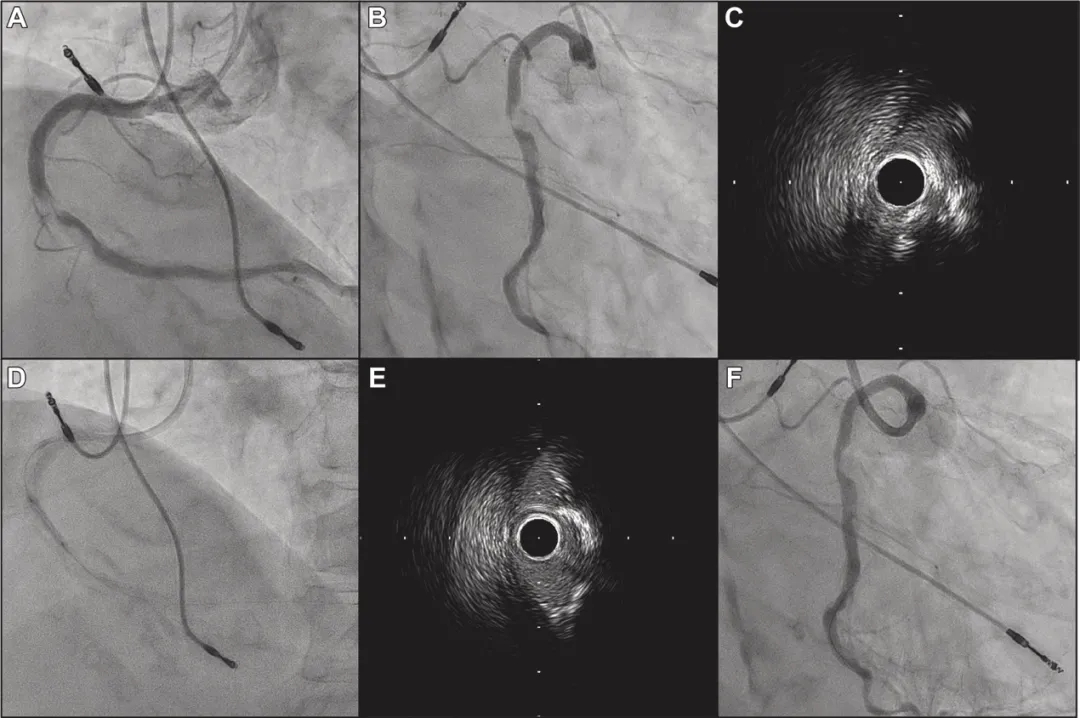

冠脉造影显示RCA中段严重狭窄伴血流延迟(图1A、1B)。IVUS于最狭窄段发现偏心性钙化结节(图1C)。使用2.75mm刻痕球囊预扩张后(图1D),冠状动脉血流改善至TIMI血流3级。但IVUS和造影均显示管腔获得仍不充分(图1E、1F),且病变预处理不理想可能导致支架膨胀不良。虽然术前考虑使用斑块减容装置处理偏心性钙化结节,但在不稳定性斑块和血栓病变上应用可能导致慢血流。为降低并发症风险,决定再次介入治疗时再行处理。

图1 急诊PCI冠状动脉造影及IVUS图像

(A)右冠状动脉中段严重狭窄伴血流延迟。

(B)右前斜/足位造影显示病变位于心室侧。

(C)IVUS显示偏心性钙化结节导致严重狭窄。

(D)使用2.75mm刻痕球囊进行预扩张。

(E)预扩张后IVUS图像。

(F)术后最终造影显示仍存在显著狭窄。